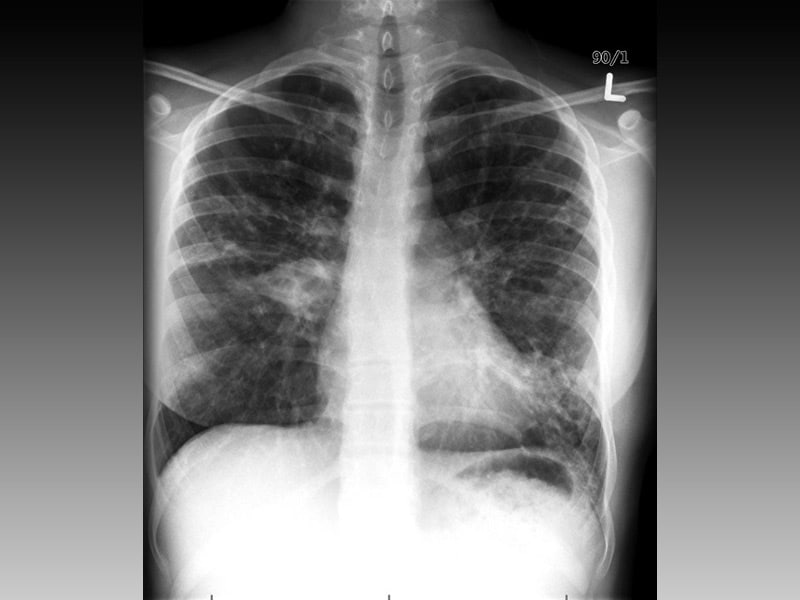

Фотографии заболеваний бронхолегочной системы